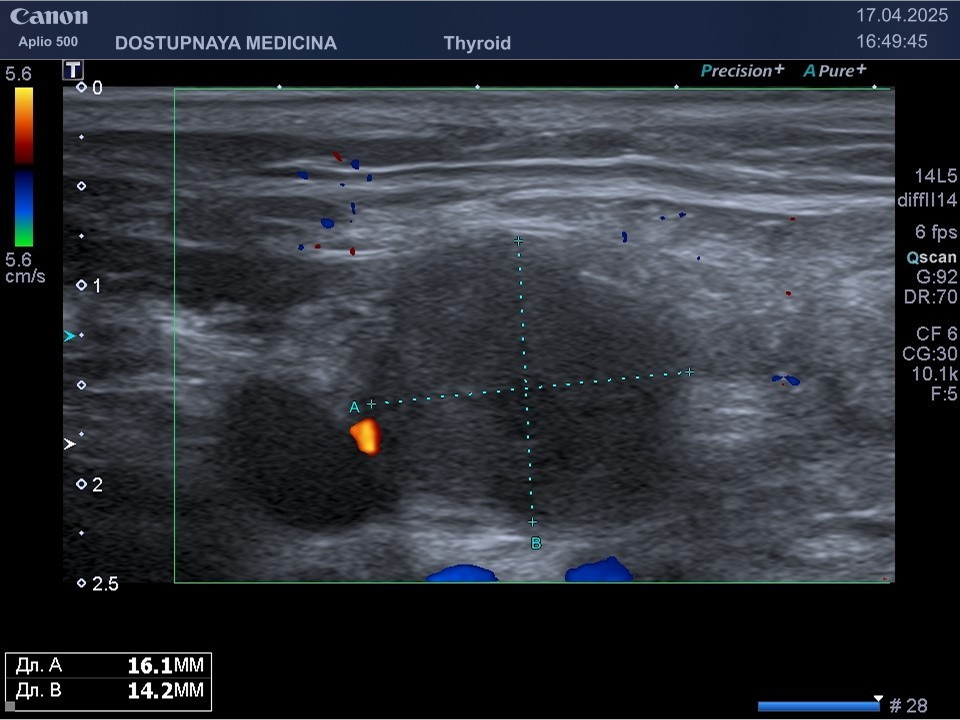

При ультразвуковом исследовании липома чаще всего выглядит, как гипоэхогенное образование овальной или округлой формы, мало отличающееся по своей эхоструктуре от окружающей её подкожной жировой клетчатки, без кровотока в режиме ЦДК. В описании заключения важно так же отметить прилежит ли близко опухоль к какому-либо кровеносному сосуду или нерву.